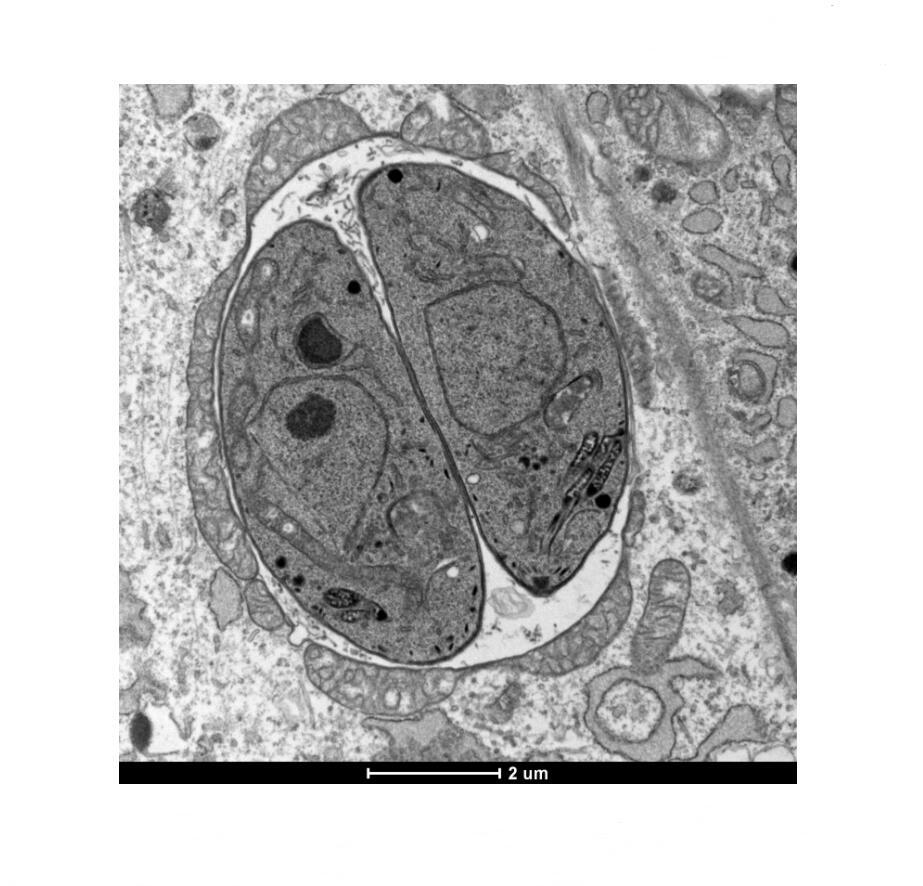

Neurotrophic pathogens have also been tied to the development of Parkinson’s disease, myalgic encephalomyelitis (ME/CFS) [152,153], multiple sclerosis [154], schizophrenia, and even epilepsy [155]. For example, Dourmashkin et al. used both transmission electron microscopy and immunohistochemistry to study autopsied brain samples obtained from patients with late-stage Parkinson’s disease [156]. They identified virus-like particles and enterovirus antigens in Parkinson’s brainstem neurons (Figure 5).

Figure 5. Transmission electron microscopy image showing intranuclear virus-like particles (VLPs) lining the internal face of the nuclear membrane of neurons in the Parkinson’s brainstem. The nuclear membrane is indicated by a thick arrow. VLPs are demonstrated by thin arrows. Reproduced from [149], an open access article distributed under the Creative Commons Attribution 4.0 International License (http://creativecommons.org/licenses/by/4.0/).